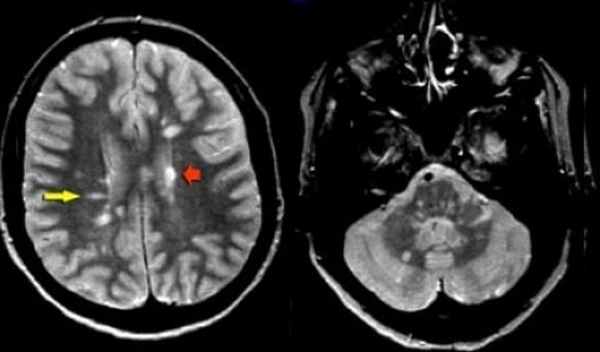

Признаки рассеянного склероза на МРТ головного мозга манифестируют себя следующим образом:

- появлением новых очагов и увеличением старых;

- во время обострения проведение МРТ головы с контрастом будет приводить к тому, что очаги демиелинизации будут накапливать контраст причудливым кольцевым способом.

Как распознают рассеянный синдром на снимках? При рассеянном склерозе на снимках заметно характерно типичное распределение очагов в белом веществе головного мозга. Кроме того, для данного диагноза характерно поражение мозолистого тела, дугообразных волокон, височных долей, мозгового ствола, мозжечка и спинного мозга. Такое распределение очагов нехарактерно для иных патологических процессов, поэтому трудностей при постановке диагноза обычно не возникает. При ангиопатии возможны поражения ствола мозга, однако они обычно симметричны и располагаются центрально, в то время как очаги при рассеянном склерозе локализованы по периферии.